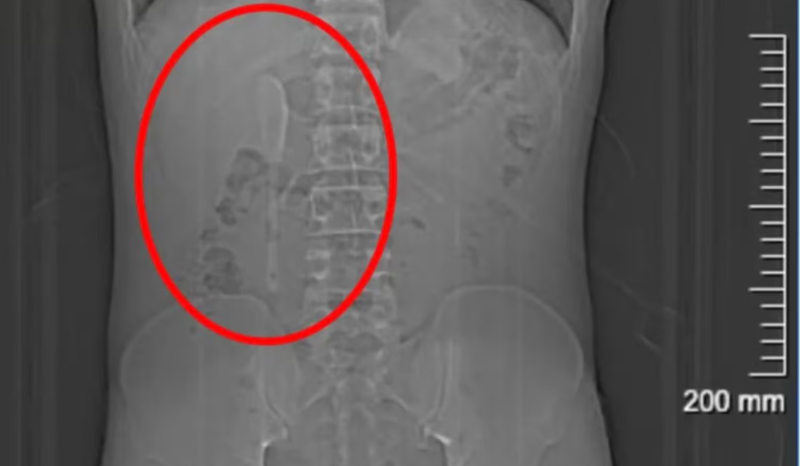

Durante os cinco meses seguintes, Yan continuou sua rotina normalmente e até praticava exercícios físicos sem apresentar sintomas graves. Só em junho, ao desconfiar que poderia ter ingerido algum plástico junto com comida de delivery, procurou um hospital em Xangai, onde exames revelaram a colher de 15 centímetros presa em uma posição delicada dentro do duodeno.

Os médicos explicaram que a extração seria difícil devido à superfície lisa da colher e à localização que colocava o intestino em risco de perfuração, podendo causar inflamação ou hemorragia intensa. A cirurgia endoscópica durou cerca de nove horas e envolveu o uso combinado de dois tipos de pinças para puxar a colher de volta ao estômago e, em seguida, removê-la.